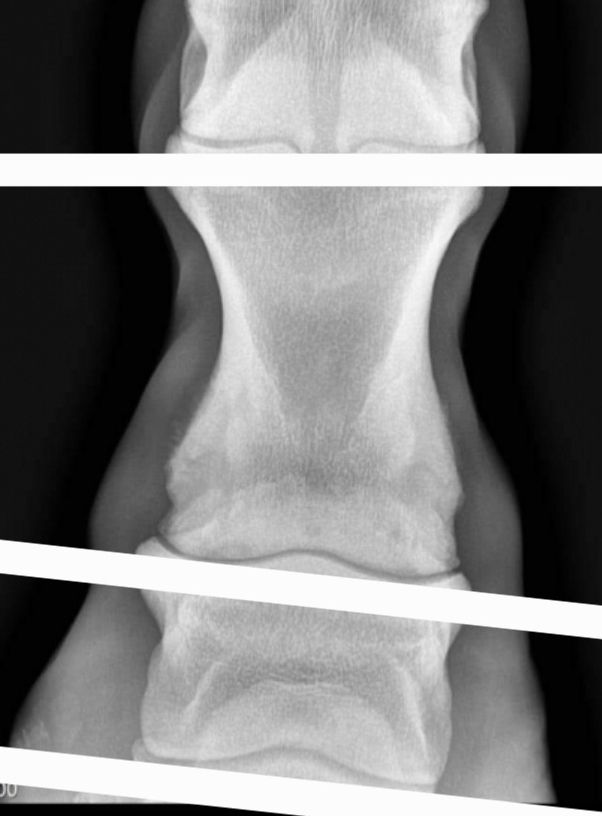

| Dire merci | ![]() Avec ce genre de radio, et légère déformation du paturon est ce que quelqu'un aurait une une idée des risques? Le cheval ne boite pas. C'est pour ma culture personnelle |

| Dire merci | L’extrémité distale de P1 me semble quand même très remaniée ? ![]() Enfin je ne suis pas experte en lecture de radio, mais le bord latéral est pas bien joli je trouve. Bon clairement, vu le cheval, les clichés, le contexte… c’est peut être pas l’idée du siècle Ça serait intéressant de faire un post de lecture de radios, avec le CR ensuite. Ça peut être instructif ![]() |

| Dire merci | Moi je dis qu'une radio juste de face bonjour bonsoir pour interpréter quelque chose a fortiori si on a pas l'autre membre. |

| Dire merci | Sur cette radio, perso je vois un affaissement de p3 et p2 par rapport a p1. Car p1 est bien parallèle au sol, alors que p2 et p3 sont inclinés :![]() J'imagine que le cheval compense la mauvaise repartition des charges dans le pied pendant un temps sans qu'il n'y ai de conséquence visible, mais est-il possible de corriger le tir avec un bon pareur ou maréchal avant que ça ne s'aggrave et que le cheval ne boîte? Aucune idée. Avis aux spécialistes? |

| Dire merci | J'ai des radios des boulets de Grimm que je suis retourné voir pour comparer. Je trouve les radios de mon poney plus jolies, avec mon oeil de béotien, et il a, je cite le rapport : Remodelage péri articulaire des boulets, épaisseur des cartilages faible, sclérose de l'os sous chondral. Ici, le souci je le vois sur P2, sur le bas, avec un remodelage non ? Sans doute consécutif à ce que souligne très justement pam Mais aussi en haut de P2. Mon poney a peu de cartilage selon le rapport, mais il y a plus "d'espacement" entre les os comparé au cheval noir. Je vais essayer de mettre des photos du mien, sachant que j'ai tout sur un PDF, donc ce n'est pas commode à extraire. Je précise bien que la radio portait sous les boulets, je n'ai pas plus bas sur ce type de vue arrière pour vraiment comparer. Et oui, ce sont de petites baguettes de Welsh B, pas la même épaisseur d'os J'avais fait des radios car je trouvais que ses boulets postérieurs avaient tendance à craquer, et il y a une gêne effective. La véto, au test locomoteur, m'a dit qu'elle aurait émis un avis positif sur une visite d'achat. Après radios, elle était plus réservée sans que ce soit une cata non plus. ![]() ![]() |